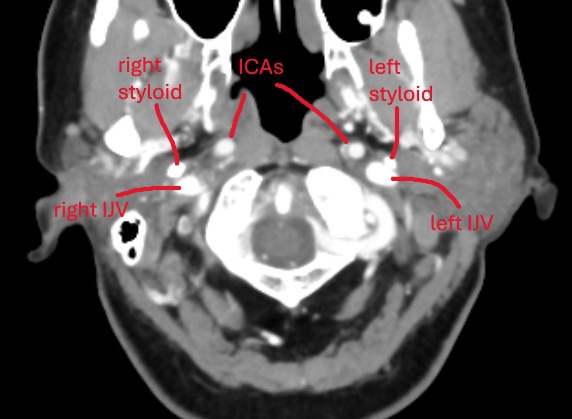

@chrEagle see attached annoted images (5 here of the axial view, and a 3D model in a following post)

Between the skull-base and C1, your left styloid comes in contact with your left IJV. Contact is normal, compression is not. I would be surprised if this contact is causing any symptoms.

Further down, at the level of C1, there is some compression of your left IJV against C1. Neither styloids are contributing to any compression here.

At the level of C2ish, your left IJV becomes compressed by your left ICA. Your ICAs are tortuous, in that they move from an anterior to posterior position and then go back to anterior position. On it’s way to to the posterior position, the left ICA compresses your left IJV.

There is no other IJV compression anywhere.

Further down, your thyroid cartilage is in contact with you CCAs. This can commonly occur, but this positioning could cause symptoms when turning your head because the SCMs contract and could push the CCAs harder against the thyroid cartilage. Symptoms would most likely include pain the radiates up the sides of the neck and down into the top of the chest.

@chrEagle those are logical explanations I think! The compression by your digastric looks worse on the left (seen in image #3). Where I have labelled your left ICA and left IJV, the IJV is pancaked between the left ICA and the posterior digastric. The posterior digastric touches the right IJV as well, but compression is not as bad. I think it moreso has to do with your left ICA pushing your left IJV into the digastric. Because on the right side you don’t see compression by digastric, but you also don’t see compression by the ICA. So I think the tortuous left ICA is a pretty significant culprit here.